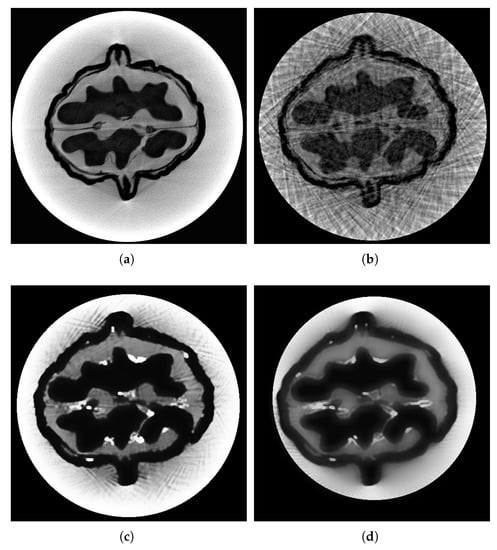

3.2. Sparse Reconstruction of Digital Brain Phantom

The digital brain phantom, widely employed for evaluating CBCT reconstruction, was used for validation. We sampled 90 projection images using the forward method through the TIGRE Toolkit and added noise with a level of . The original digital brain slice served as a benchmark for CBCT reconstruction. Additionally, four classical methods discussed in the introduction—FDK, OS-SART, ASD-POCS, and ordered subset ASD-POCS (OS-ASD-POCS)—were used for comparison.

Figure 4 illustrates voxel curves and their local magnifications along the coronal axis (256th row, 160th slice) and the vertical axis (256th column, 160th slice). As depicted in Figure 4b,c, the proposed method performs substantially better than FDK and OS-SART for smooth segments, which have curves heavily disturbed by noise. As seen in Figure 4e,f, the proposed method outshines ASD-POCS and OS-ASD-POCS for steep segments, with curves significantly affected by noise.

Figure 4.

Voxel curves reconstructed by various algorithms: (a) voxel curve along coronal axis at 256th row, 160th slice, (b,c) local magnifications of (a); (d) voxel curve along axial axis at 256th column, 160th slice; (e,f) local magnifications of (d).

Concurrently, evaluation results are provided in Table 1 using RMSE, PSNR, and SSIM. From the perspectives of PSNR and SSIM, the proposed method and the ASD-POCS method exhibit high structural similarity and signal-to-noise ratio. Regarding RMSE, the proposed method is slightly higher than ASD-PCOS, potentially due to the addition of WSNM noise reduction, increasing the error from the ground value. Considering all three indicators, the proposed method excels in terms of signal-to-noise ratio and structural similarity, with a minor disadvantage in RMSE but a small difference.